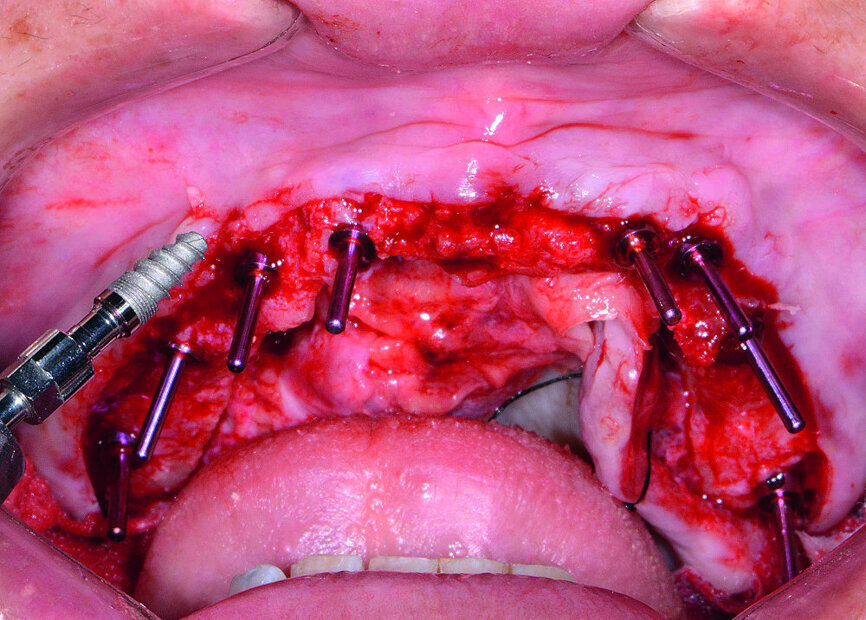

Au cours de la visite prévue pour la chirurgie, une sédation intraveineuse a été administrée à la patiente. Après le décollement d’un lambeau tissulaire, le guide chirurgical à appui osseux a été ajusté sur le maxillaire et les tenons de fixation ont été serrés (Fig. 9). Les ostéotomies implantaires ont été pratiquées selon le protocole chirurgical simplifié du système d’implants coniques Hahn. Huit implants ont été posés dans le maxillaire, le long du segment de l’arcade délimité par les deuxièmes molaires (Figs. 10 et 11). Des piliers de cicatrisation ont été connectés aux implants, afin de favoriser la préparation du tissu mou pour la phase de restauration (Fig. 12).

Ensuite, les dents mandibulaires, qui étaient irrécupérables (Fig. 13), ont été extraites à l’aide du davier Physics Forceps (GoldenDent), un lambeau a été décollé et une alvéoloplastie réalisée. Un guide chirurgical à appui osseux a été mis en place pour vérifier l’emplacement et l’angulation des ostéotomies implantaires (Fig. 14). Étant donné que les implants coniques Hahn sont pourvus d’un filetage auto-taraudeur, les filets profonds et tranchants, pénètrent dans les parois des sites alvéolaires et permettent de maintenir l’implant dans la position appropriée, par rapport à la paroi linguale. À la suite du nivellement osseux, on pouvait s’attendre à un gonflement des tissus, et des piliers de cicatrisation de 5 mm de hauteur ont donc été connectés aux implants de l’arcade mandibulaire (Fig. 15). Les prothèses immédiates ont été rebasées avec un matériau souple (Mucopren, de Kettenbach) afin de les insérer sur les piliers de cicatrisation, dont la forme en sablier et les zones rétentives assurent un degré de rétention qui améliore la fonction dentaire pendant la cicatrisation (Fig. 16).